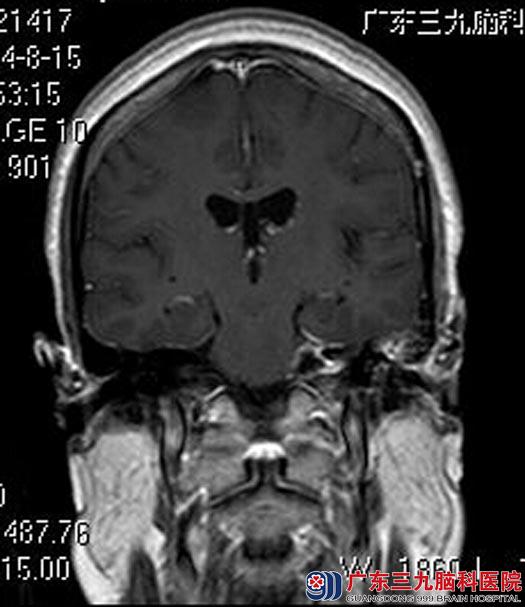

全麻下行左侧桥小脑角占位病变切除术,显微镜下见肉红色肿瘤组织,包膜完整,被小脑前下动脉包绕,质中,血供丰富,肿瘤与面听神经及脑干粘连明显,予分离后行肿瘤全切,术中对三叉神经、面神经、听神经、脑干均保护完好。手术后周女士耳鸣症状较前好转、康复出院。术后病理结果:听神经瘤。

手术后